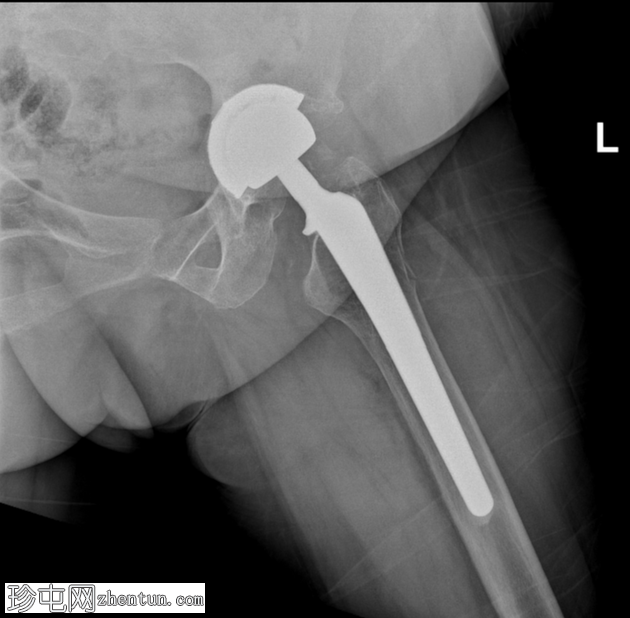

X线片

正位片

双侧全髋关节置换术假体完整,无松动迹象。

左侧股骨大转子下区外侧皮质中断,侧位片显示最佳,提示假体周围骨折。